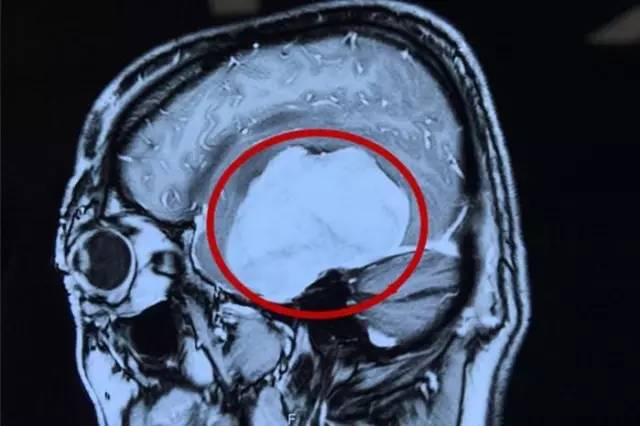

術(shù)前影像資料:紅圈內(nèi)白色部分為腫瘤物

這名患者叫虞文軍(化名),57歲,浙江寧波人。三個(gè)月前虞文軍右側(cè)手臂肘部至肩部出現(xiàn)酸痛,上舉無(wú)力,持續(xù)時(shí)間不長(zhǎng)后緩解,因此便沒(méi)在意。半個(gè)月前,虞文軍在開車時(shí)再次突然出現(xiàn)手臂酸痛無(wú)力癥狀,致使方向盤失去控制發(fā)生車禍連撞三車,所幸并無(wú)人員傷亡。虞文軍這才意識(shí)到問(wèn)題的嚴(yán)重性,至當(dāng)?shù)蒯t(yī)院就診,行頭顱CT檢查示:左側(cè)顳區(qū)底部大腦凸面可見類圓形略高密度占位病變,周圍見低密度水腫影,CT值為44HU,大小約為8*6cm,周邊腦組織及腦室受壓,中線結(jié)構(gòu)右移,額頂部軟組織腫脹,考慮為左側(cè)底部腦膜瘤。

為求進(jìn)一步治療,經(jīng)過(guò)四處打聽,虞文軍在愛人的陪同下于4月22日前來(lái)我院就診。我院神經(jīng)外科專家潘仁龍主任接待了虞文軍。入院后行頭顱MR+增強(qiáng)及MRA發(fā)現(xiàn):腫瘤供血豐富,供血起源于小腦幕上動(dòng)脈。